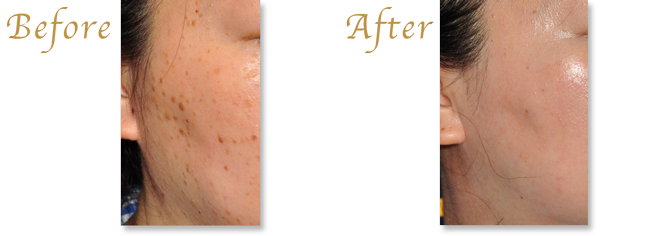

ニキビとは

毛穴が角質成分でふさがれた状態が、いわゆる「黒ニキビ」「白ニキビ」です。

ここに、皮脂分泌の増加や細菌感染などが加わると、毛包が膨らみ、炎症を起こして「赤ニキビ」となります。

「赤ニキビ」になると、炎症は毛包周囲に及び、ひどい場合には炎症が治まってからも瘢痕(きずあと)として皮膚が硬くなったりくぼんだりする「ニキビ痕」の状態となってしまいます。

痕を治すのは非常に大変なので、まずはニキビの発生を抑え、生じてしまった炎症は早く終息させることがニキビ治療の根本となります。

治療を受けていないニキビの多くは、保険診療で改善します。